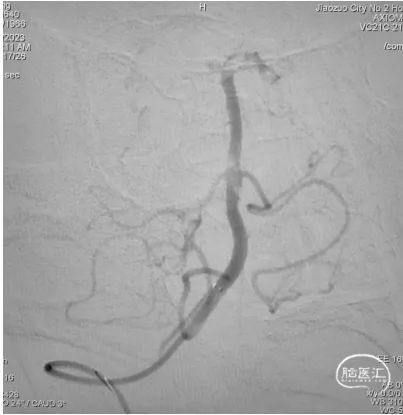

DSA提示:右侧大脑中动脉M1段以远闭塞,右侧大脑前动脉皮层支少量代偿,右侧大脑前动脉A3段血栓影,远端流速可,基底动脉尖端未见显影,考虑急性闭塞。

6F心玮吞川®颅内血栓抽吸导管同轴配合8F心玮天梯®支撑导管在泥鳅导丝导引下放置于右侧颈内动脉眼段。

微导丝配合微导管沿颅内血栓抽吸导管小心通过右侧大脑中动脉血栓段,微导管造影示右侧大脑中动脉远端血流通畅。

确定血栓长度后,以4.0*30mm颅内取栓支架行右侧大脑中动脉取栓配合中间导管抽吸。

造影提示右侧大脑中动脉血流通畅。

取栓装置中可见白色胶冻状血栓。

6F心玮吞川®颅内血栓抽吸导管行基底动脉血栓抽吸。

复查造影示基底动脉及其分支显影良好,取栓装置中可见白色胶冻状血栓。